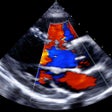

Acceso seguro a imágenes médicas en iPhone

iPaxera: Visualizador DICOM para iOS